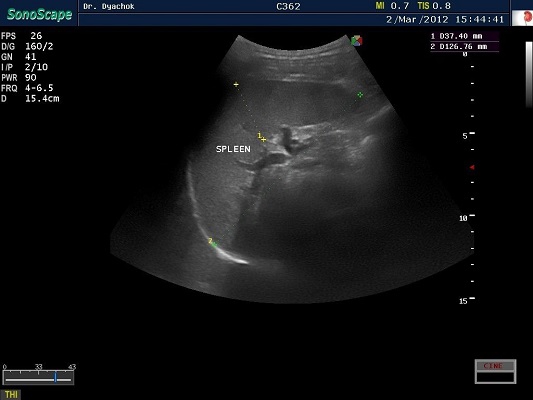

SonoScape S2N Vet – уникальная узи-система, выполненная в виде портативного ноутбука для легкой переноски. Отличается эта система цветным форматом визуализации, а также крайне чувствительными доплеровскими режимами, работающими на уровне премиальных аппаратов. При оптимальной цене – это очень хорошее и сбалансированное решение для ветеринарной клиники.

Диагональ монитора составляет 15,6 дюймов, что обеспечит комфортную работу для врачей и полный спектр визуализации для пациентов. Компактный вес не превышает 5 кг. (вместе с батареей), что оценят выездные бригады скорой помощи или ветеринары, выезжающие на дом.

Цифровая рабочая станция S2N Vet предполагает наличие жесткого диска для записи данных, составление и экспорт отчетов с возможностью добавления изображений, ведение базы данных пациентов.

Режимы сканирования SonoScape S2N Vet:

• В, М, В/М, В/В, 4В, Тканевая гармоника;

• Изменение масштаба изображения в режимах реального времени и стоп-кадра;

• Цветной, энергетический, направленный энергетический, импульсно-волновой,

• Постоянно-волновой допплер;

• Дуплексный, триплексный режимы;

• Трапецеидальное сканирование на линейных датчиках;

• Режим панорамного сканирования;

• Технология подавления спекл-шума MicroScan.